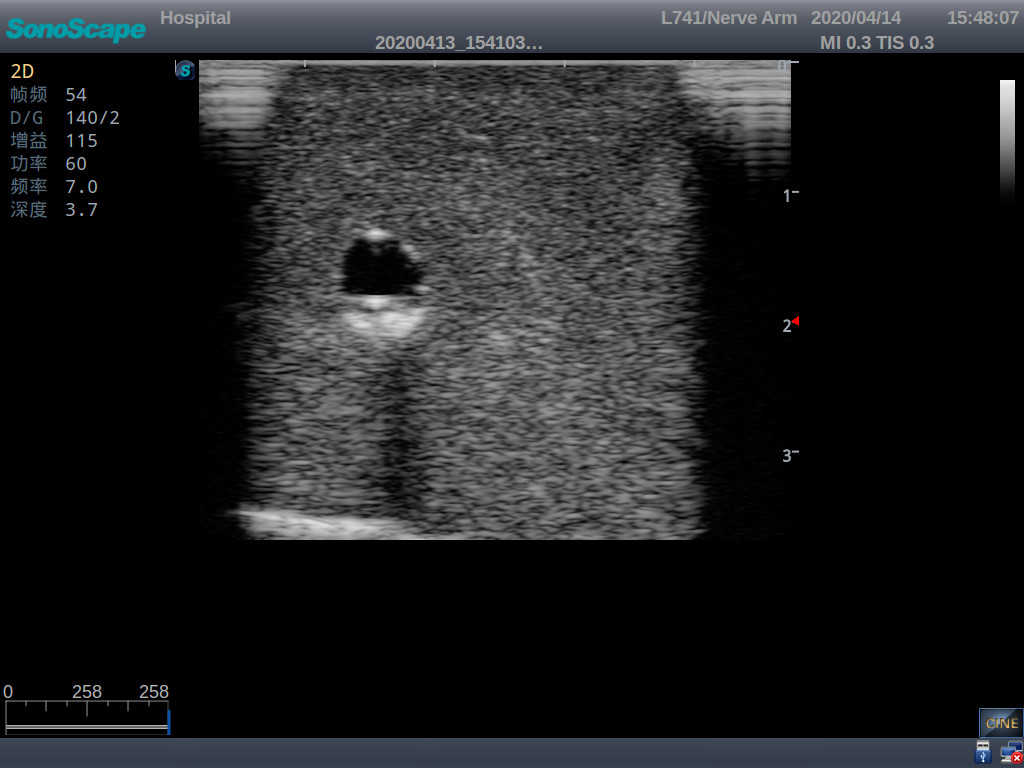

2)   It can be used by real ultrasound machines

3)   Clear and real images of the tissues and organs (basilic vein and superior vena cava)

4)   When conducting vascular puncture, the piercing can be truly felt, and venous blood outflow can be seen

6)   Detect whether the catheter is properly placed